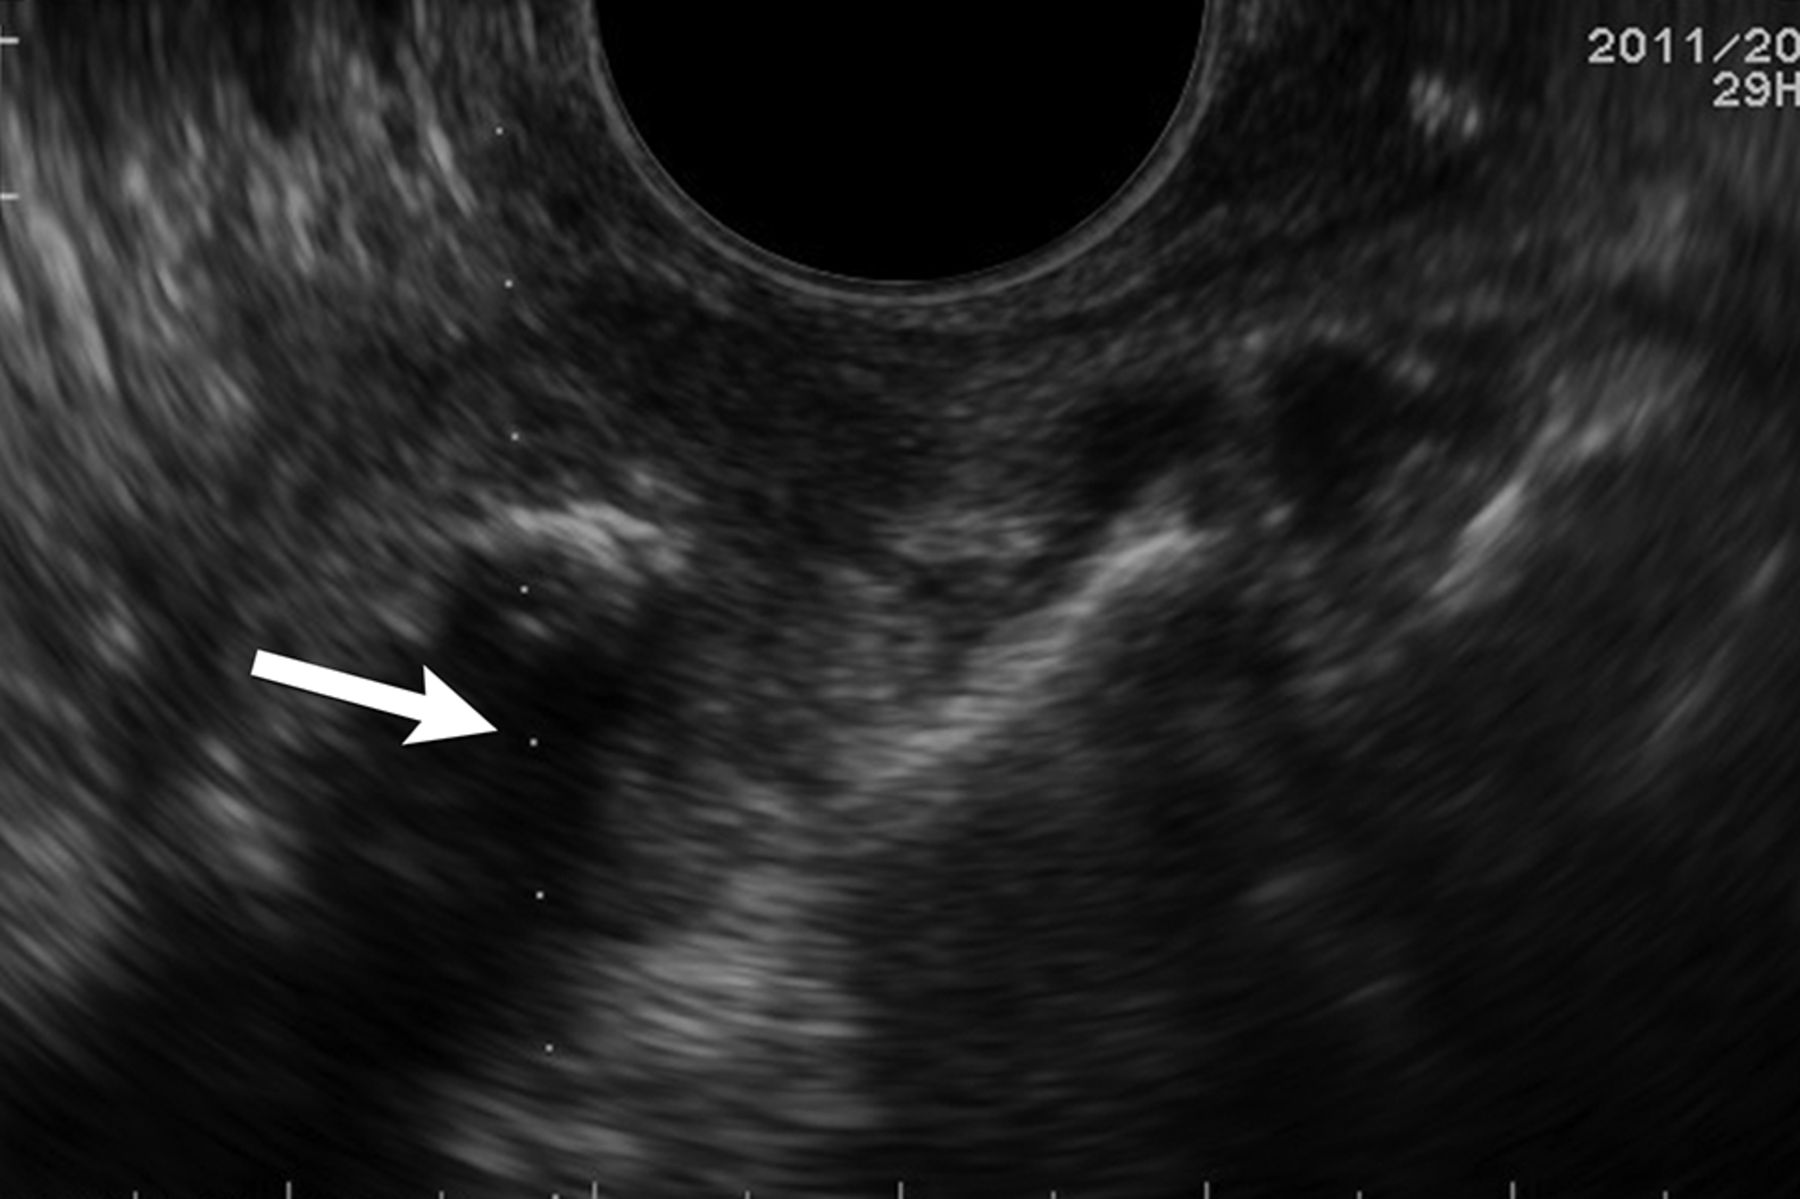

A TOUS-FNA was performed in all patients by a neuroradiologist experienced in interventional sonography of the soft tissues of the neck. The transducer, with the needle guide attached, was inserted into the oral cavity and placed in direct contact with the pharyngeal mucosa. A built-in electronic biopsy line was activated to indicate the expected trajectory of the biopsy needle. The position of the transducer was adjusted so that the biopsy line would cross the sonographic image of the suspicious retropharyngeal mass (Fig 1).

Biopsy line. Transverse sonography before biopsy of a partially calcified right retropharyngeal mass demonstrates a biopsy line and expected path of the biopsy needle through the lesion (white arrow).